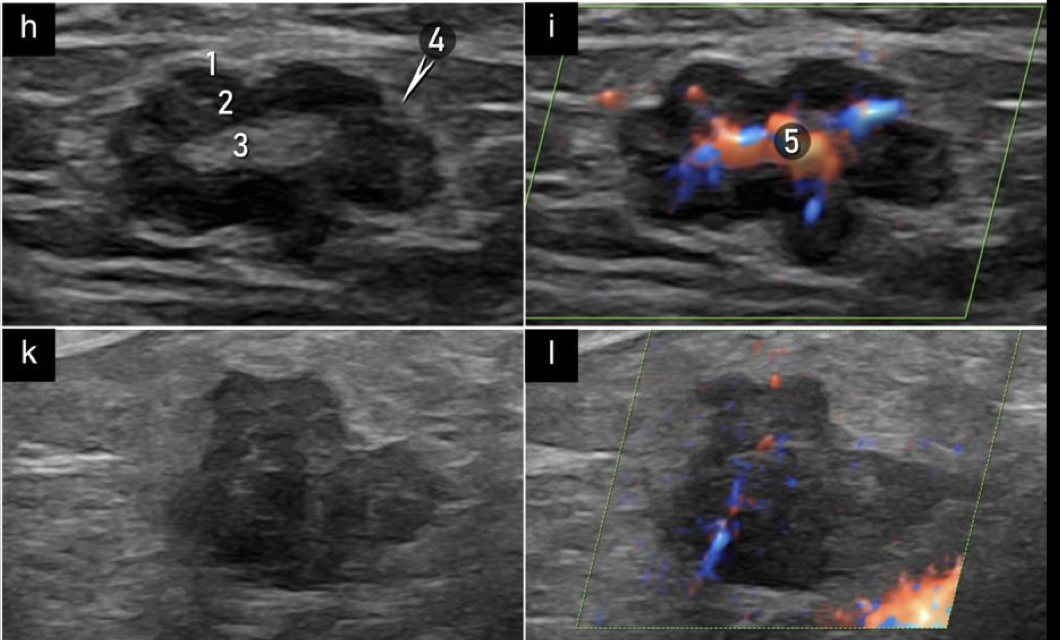

Probablemente malignos